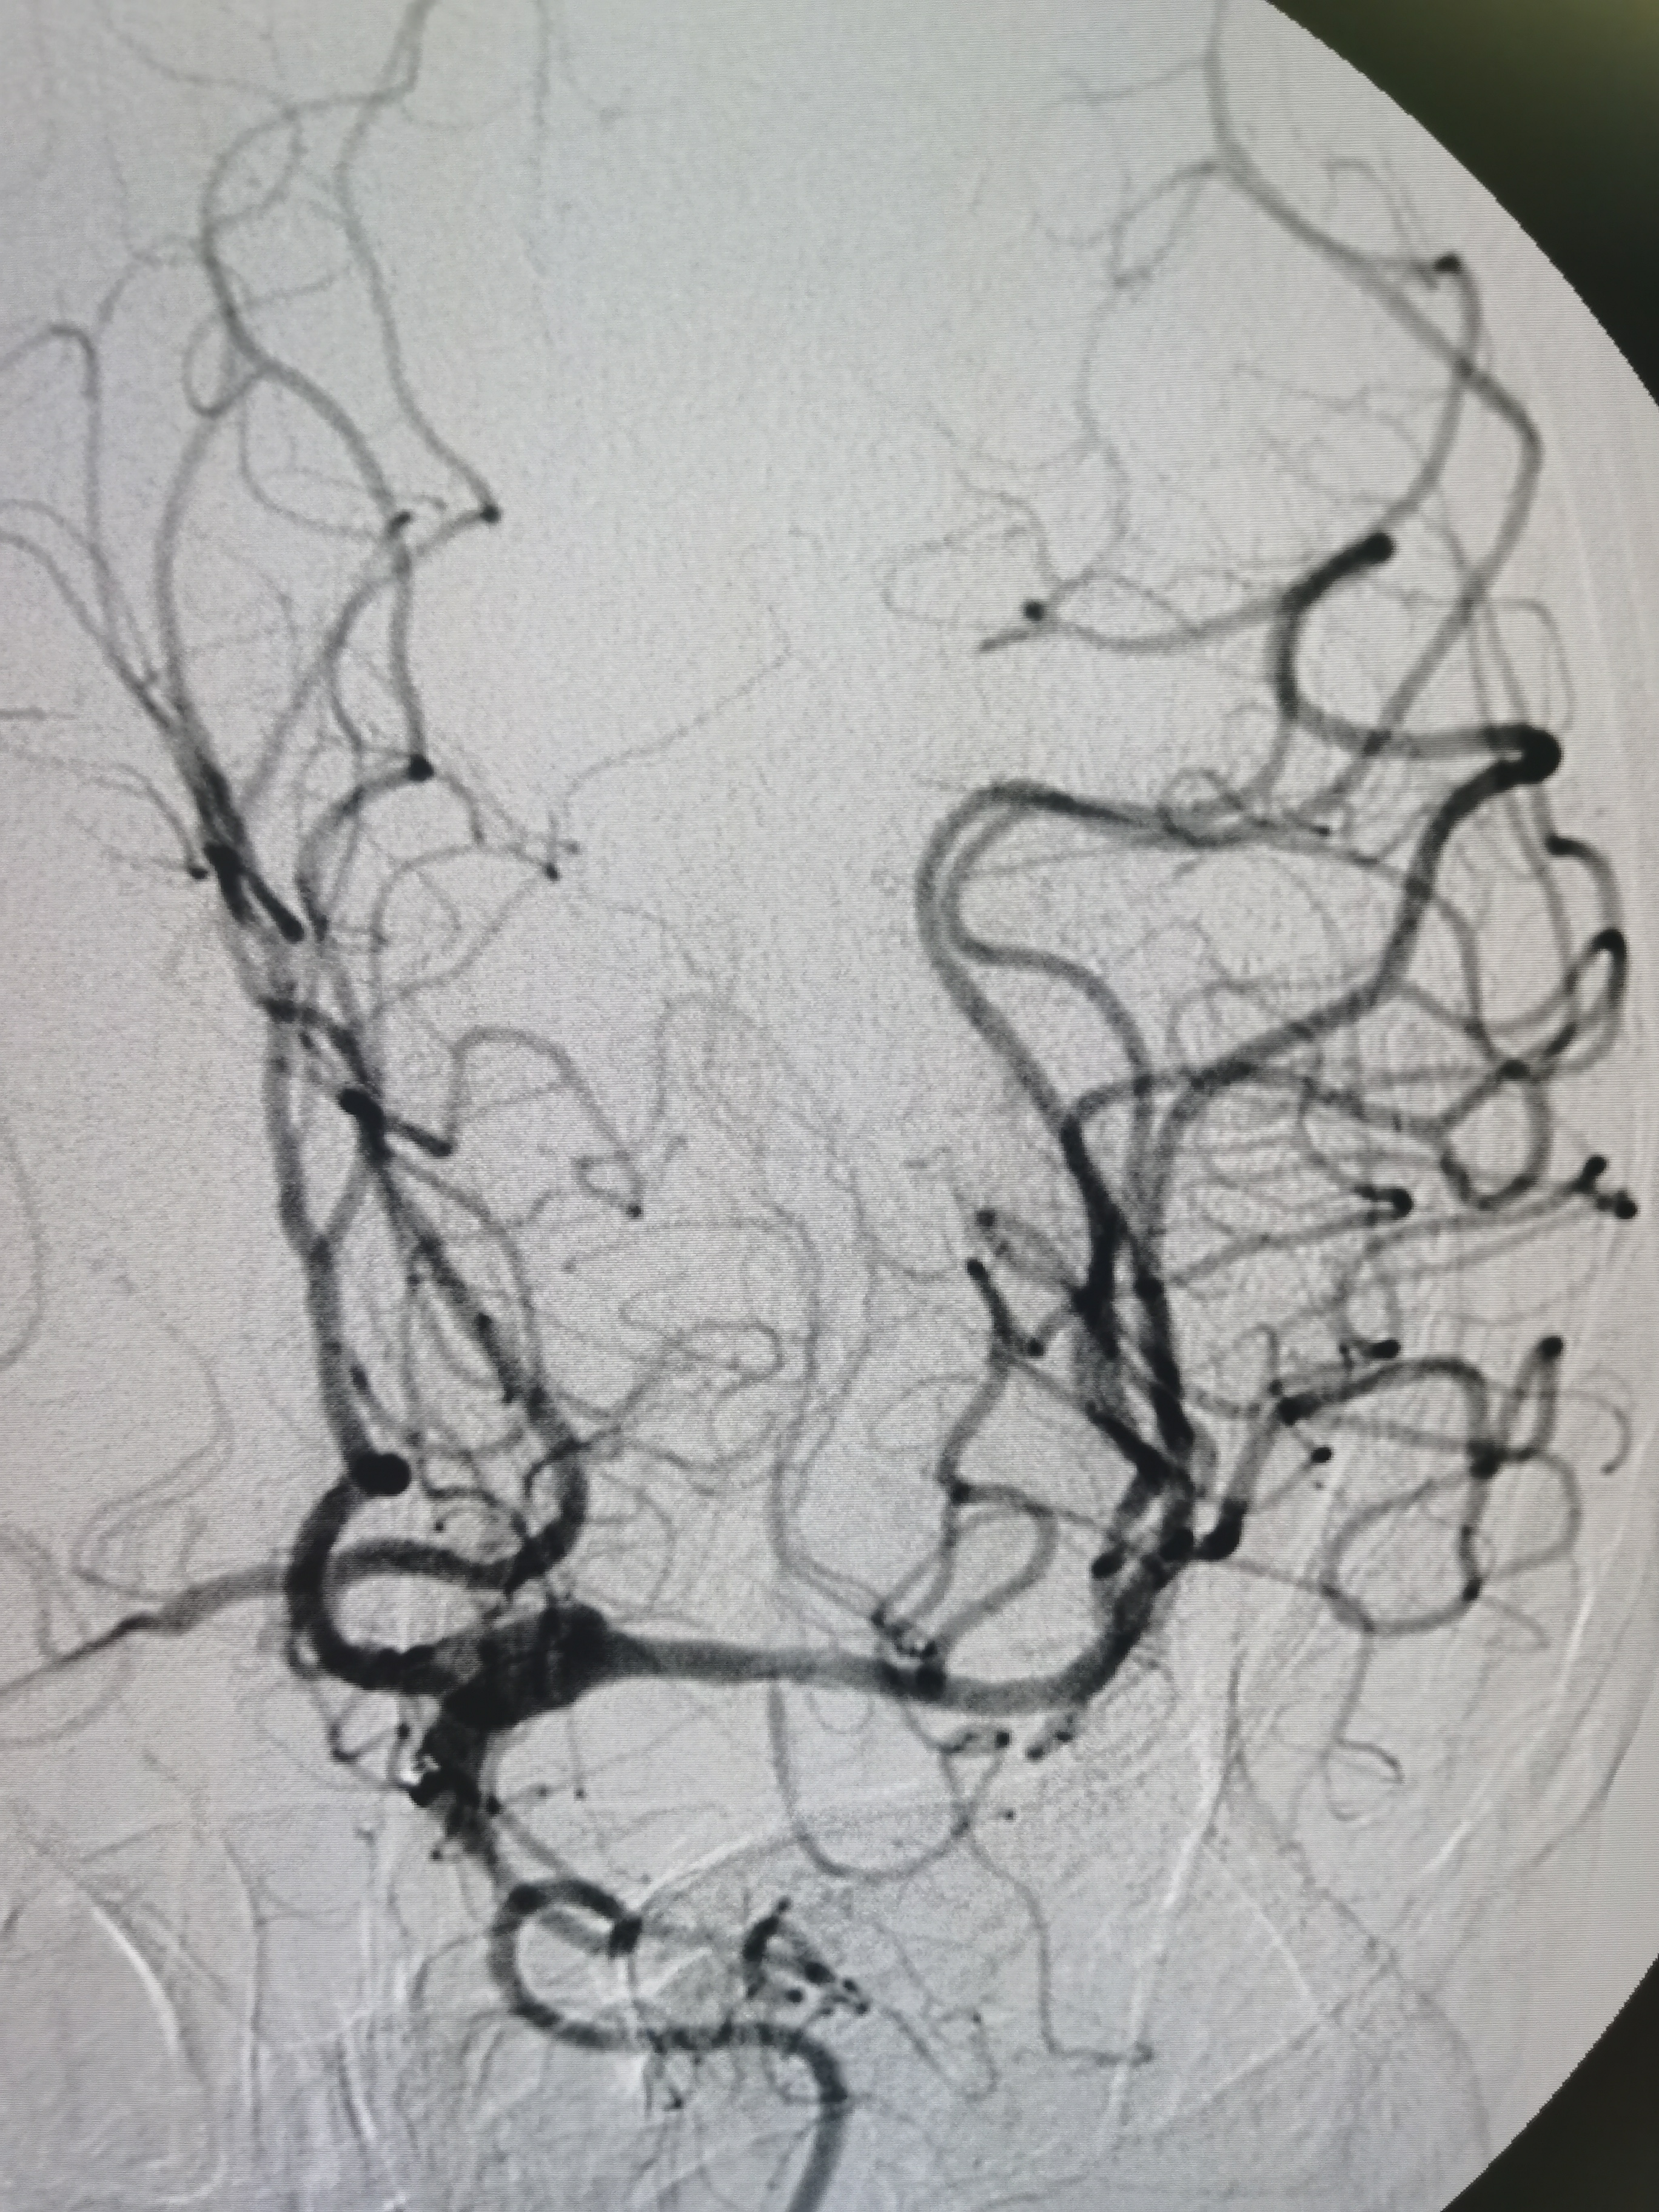

取栓后颅内血管再通,血流通畅。